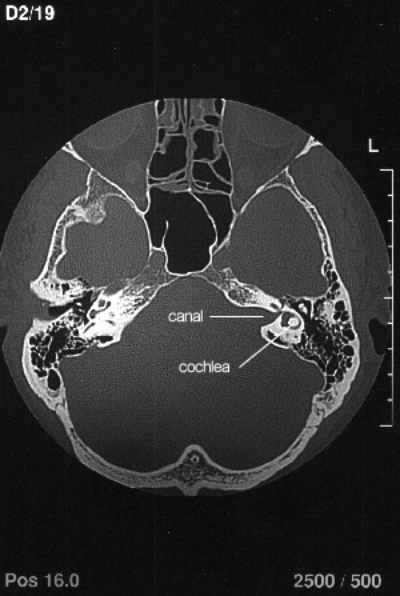

CT Scan

The CT scan shows a view similar to the MRI scan but shows up the bony structures rather than the soft tissue. The tumour sits in the canal, which is enlarged by its' presence. The cochlea shows up well in this scan. As with the MRI scan, the scale marks are at 1cm intervals. The translabyrinthine approach to removal of the tumour involves drilling through the bone behind the ear, to access the canal, destroying the cochlea in the process